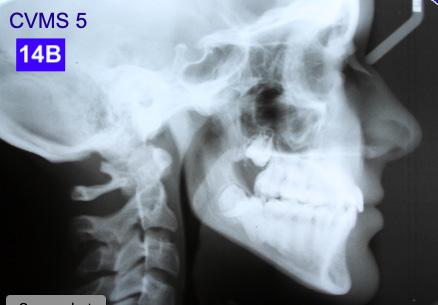

Lateral Cephalometric radiogram revealed a narrow airway in the tonsil area (5.0 mm), retrognathic maxilla and mandible (SNA - 78°, SNB - 76°), retrusive maxillary incisors (U1/SN - 91°), retrusive mandibular incisors (L1/GoM - 83°). She was Class III skeletally as ANB, Wits and the Harvold ∆ were – 2.4°, -5.0 mm and 24.8 mm The patient was hyper-divergent as seen from NS/GoM of40° and a Lower gonial angle of 79.7°. The patient was in CVMS 2 - 3 (Cervical Vertebrae Maturation Stage) (Figure 2-B) and an A-P Radiogram revealed a posterior crossbite (Figure 2-C).

Figure 2A: Pre-treatment, Panoramic radiogram Figure 2B: Pre-treatment, lateral Cephalometric radiogram

Although the treatment was a lengthy one (60 months), our outcome was favourable. The patient was finished with a skeletal class I, an Angle Class I cuspid and a Class II molar relationship with minimal overjet and overbite. ANB stayed the same however, Wits improved from -5.0 mm to 2.0 mm. ALFH increased by 7.0 mm due to the composite build-ups on the mandibular first molars and elevation of the rest of the mandibular dentition to this height. Also, the growth from CVMS 2 - 3 to CVMS 5 influenced the height of the mandibular alveolar process. The patient’s posture did not change significantly as the frontal view still revealed a slight left head tilt, and the lateral view revealed the head forward position seen previously. We postulate that the lack of greater improvement in posture relates to untreated nasal airway impingement. Olmos writes that nasal airway compromise is thought to exacerbate forward head posture, worsen unfavourable growth patterns (hyperdivergence) and contribute to mouth breathing as the patient is attempting to maintain a better airway.10 It is possible that advancement of the maxilla may have